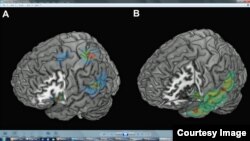

Lesion overlap analysis for the FoP group (A) revealed three regions where overlap was maximal: temporo- parietal, insular, and especially (when comparing to a control group, B) fronto -parietal cortex. ©Current Biology

Scientists at the Swiss Federal Institute of Technology in Lausanne (EPFL) analyzed MRIs of 12 patients with brain disorders who reported experiencing these apparitions. They found disturbances in parts of the brain that deal with movement and the position of the body.